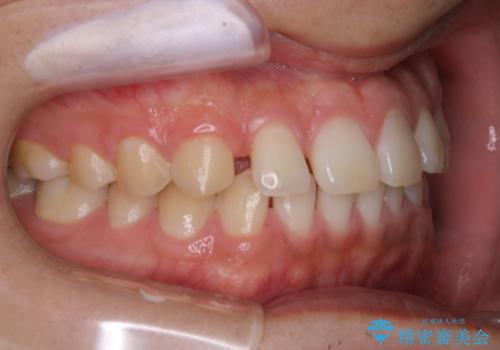

- 上のすきっ歯が気になるとご相談にいらした方です。上下顎ともにスペースがあったため、インビザラインFULLにて見た目と噛み合わせの改善も同時に行いました。

元々は上前歯のみの部分矯正をご希望されていましたが、下の歯もスペースがあり、噛み合わせ的にも上のみの部分治療は難しいことをお話ししました。前歯のみの部分矯正を行った場合、前歯の隙間だけが閉じて奥歯が噛めなくなってしまう場合もあります。インビザラインFULLにて治療することで、噛み合わせと見た目を同時に改善させることができ、大変喜んでいただけました。